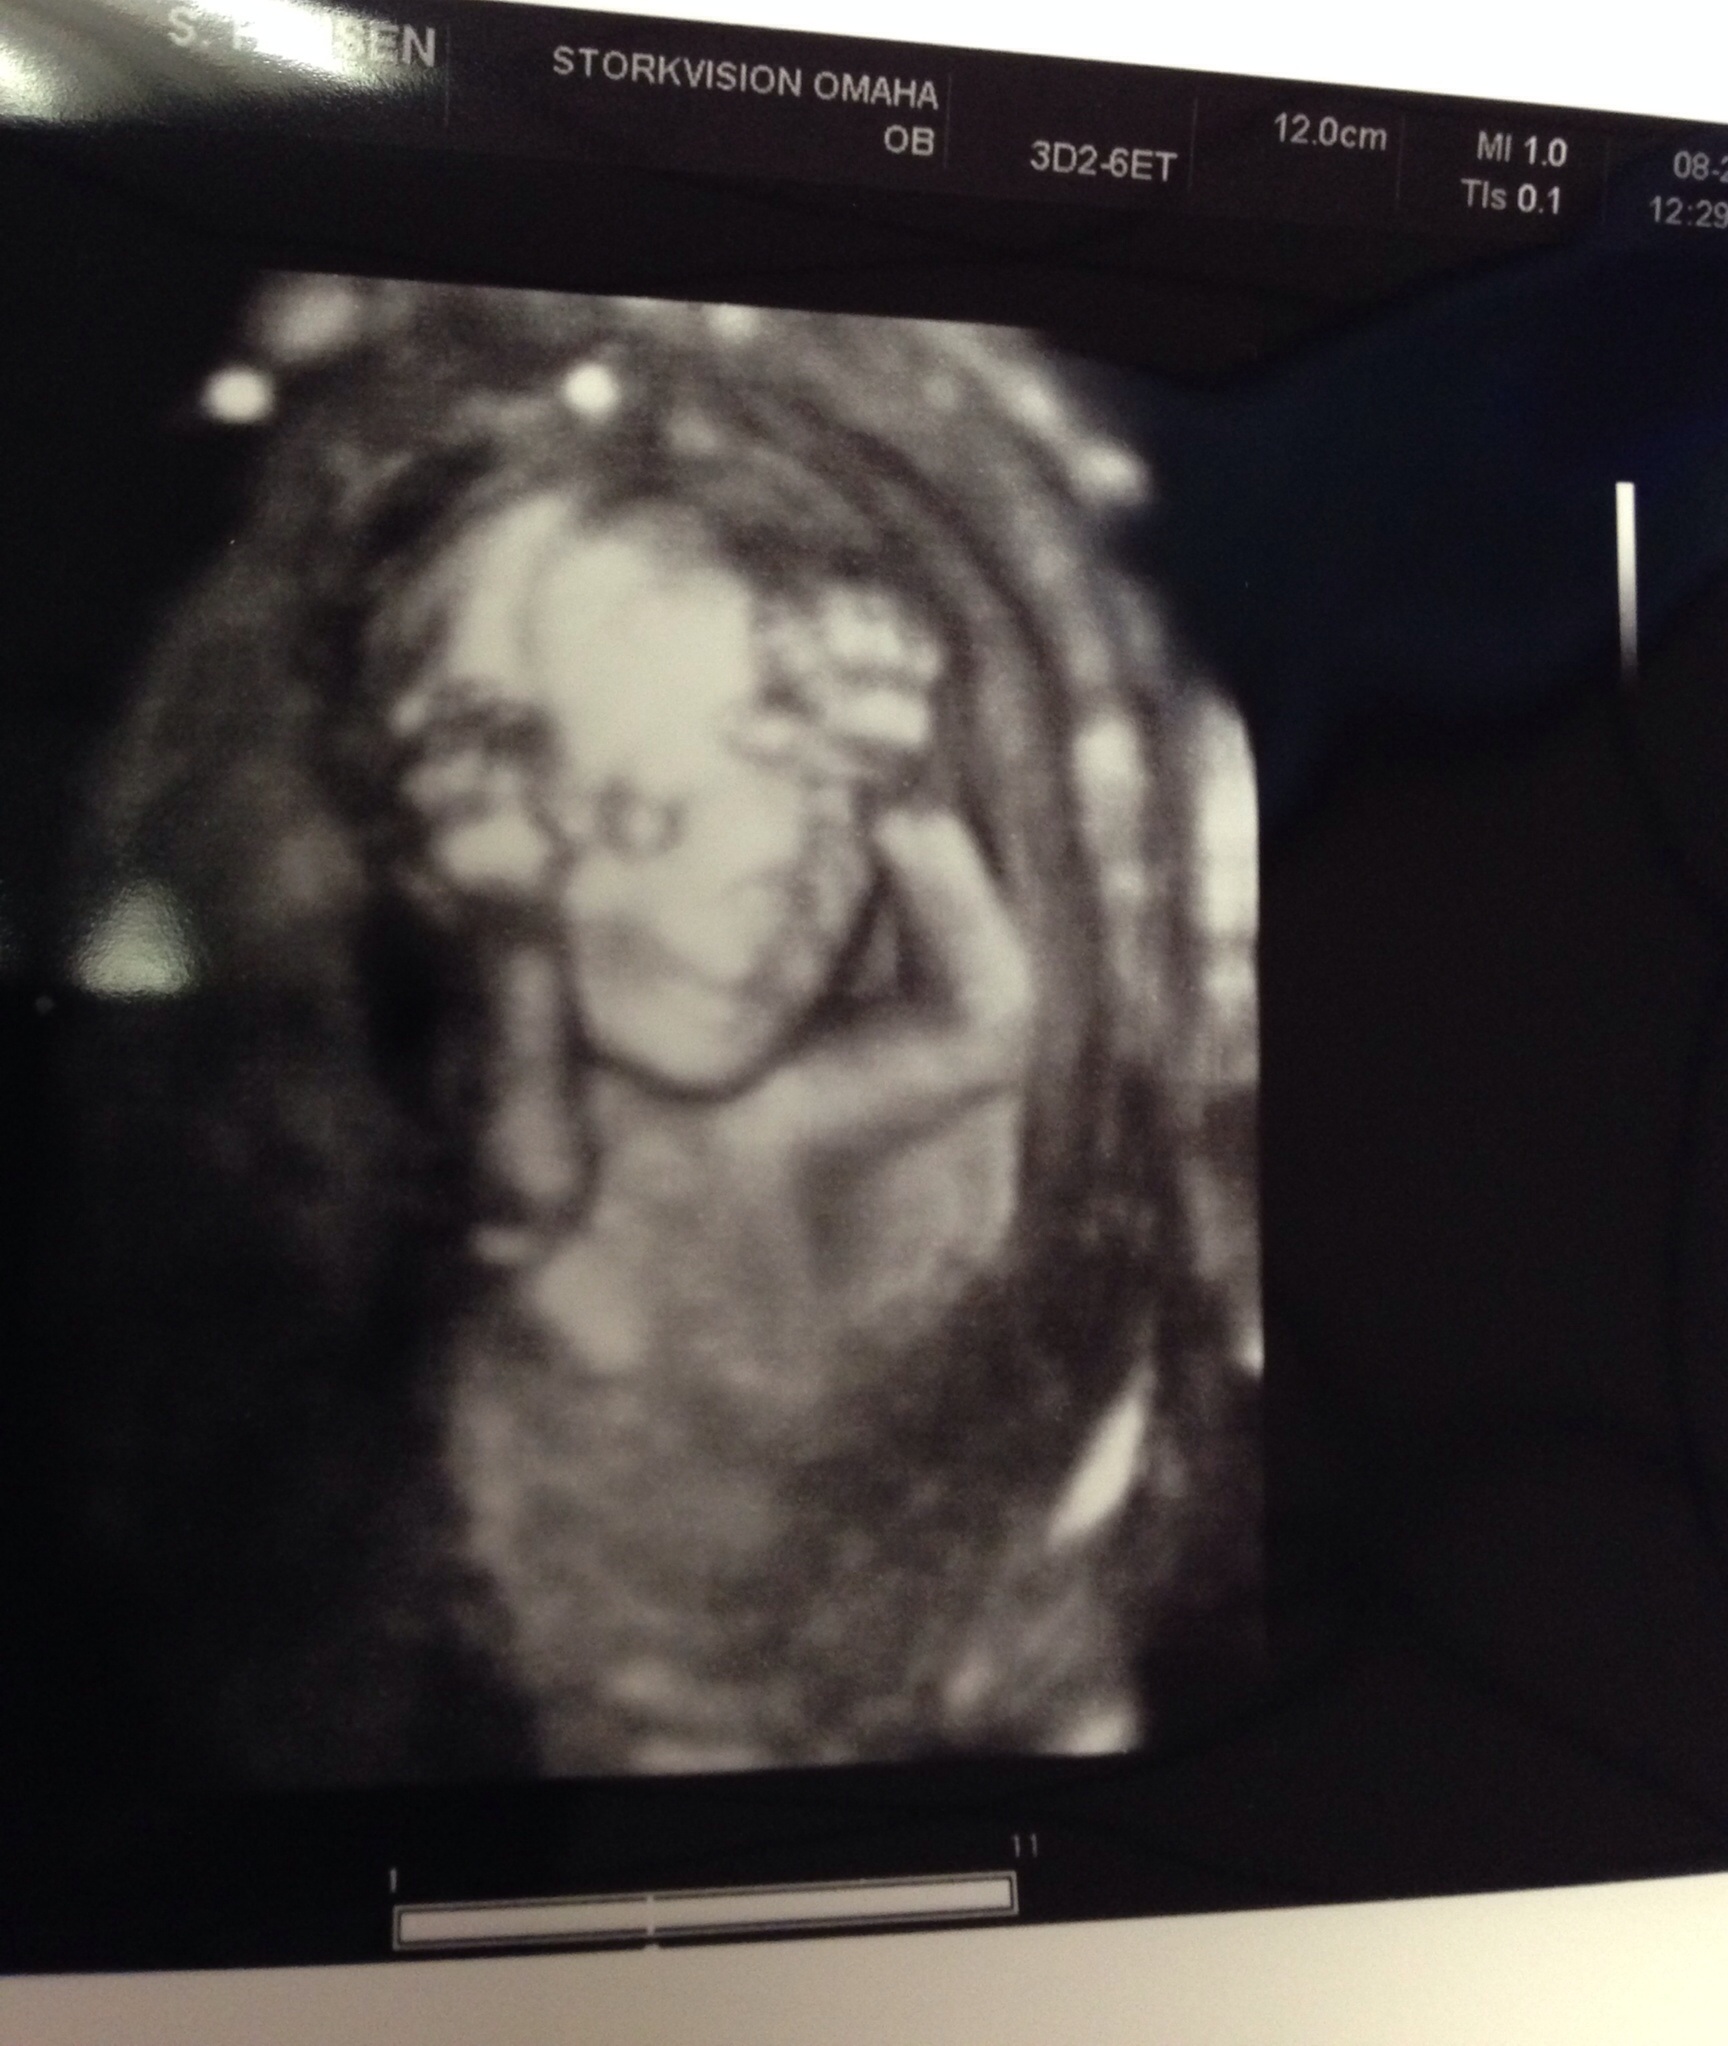

My a/s was traumatic, but all is well now and baby appears healthy. The pic is our 6 year old daughter on the left, and our current baby on the right, Vivienne Rose!